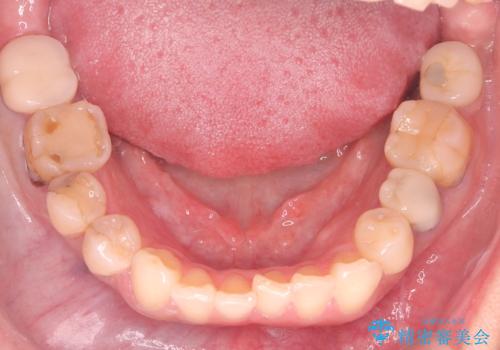

- 40代の患者様で、左上の**八重歯(犬歯の突出)**をずっと気にされていたものの、年齢的な不安から治療を迷われていたとのことでした。精密な検査の結果、左上の歯列に八重歯を収めるための十分なスペースがないことが判明。

40代は歯周組織の健康維持も重要なため、無理な拡大を避け、左上4番(第一小臼歯)を抜歯して確実にスペースを確保する計画を立てました。装置には、歯を三次元的にしっかりとコントロールでき、確実な移動が見込めるワイヤー矯正を選択。八重歯を正しい位置へ誘導し、健康的で美しい口元を目指しました。